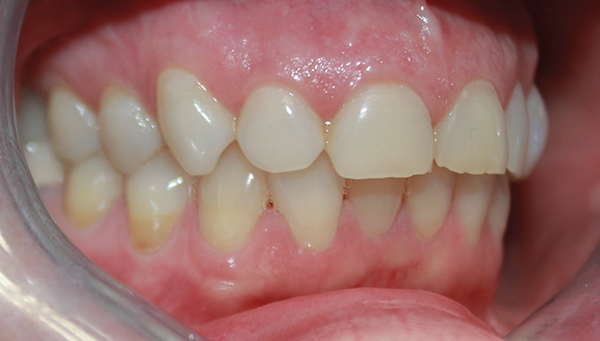

Fig 3. Preoperative lateral view.

Figure 3

After several years and many consultations, the patient finally agreed to move forward with the recommended treatment. The patient's pretreatment condition is depicted in Figure 1 through Figure 3. Upon evaluation, several conditions were documented. The observation of a more coronally positioned gingival margin on the maxillary anterior teeth was noted. The differential diagnosis of dentoalvealor extrusion versus altered passive eruption was considered. The process of altered passive eruption was ruled out after appropriate bone sounding and palpation of the cemento-enamel junction (CEJ) apical to tooth Nos. 7 through 10. The gingival margin and bone heights were determined to be localized in a normal position within the gingival sulcus. This confirmed the diagnosis of dentoalveloar extrusion.10 As the linguals of the upper teeth were destroyed with acidic exposure, the teeth continued to erupt into function. Observations also included buccal collapse of the arches, malalignment of teeth, incisal wear, and dentoalveolar extrusion of the lower anterior teeth. A thorough smile design work-up was completed using numerous intraoral and extraoral radiographs and photographs. The lower incisal edges, particularly of tooth Nos. 24 and 25 showed signs of extrusion and wear but since the incisal edges closely followed the curvature of the lower lip line and the patient was only interested in maxillary treatment, their intrusion was limited to leveling and aligning the incisal edges. The preferred treatment option in this type of case is to consider orthodontic intrusion of maxillary teeth to relevel the gingival margins and subsequently increase occlusal clearance between arches for restorations. At that point, a treatment plan was developed that would address incisal edge position, which had shortened over time, and the appearance of gingiva versus tooth structure during a full smile.11 In addition, the photographs were used to evaluate the curvature of her smile, the midline of the teeth to the face, and the overall esthetics of the smile.

Fig 1. Maximum intercuspation showing worn incisal edges and altered gingival curvature of the maxillary arch at patient’s initial presentation.

Figure 1